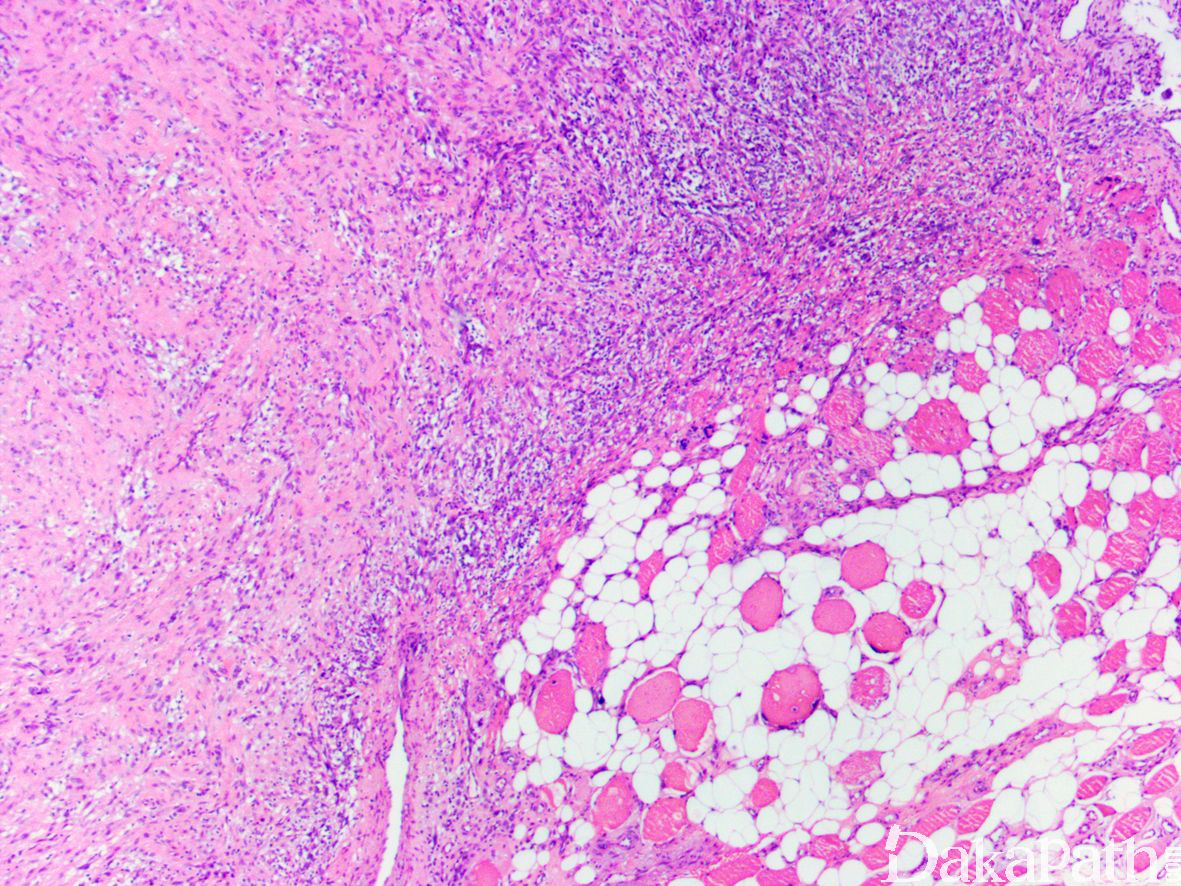

镜下肿瘤界限不清,梭形瘤细胞较密集,呈平行的束状和片状排列,肿瘤一致性的显示向周围脂肪组织和骨骼肌组织内不同程度的浸润性生长,组织学构型类似于脂肪纤维瘤病;

瘤细胞胞浆嗜酸性,胞膜界限不清,核呈纺锤状,可见轻度的核非典型性和核浓染,核仁不明显,散在可在多形性肿瘤细胞;

尽管瘤细胞密度较高并可见多形性,但核分裂少见,通常< 2 个/10 高倍镜视野,偶尔可达 8 个/10HPF,未见肿瘤性坏死。